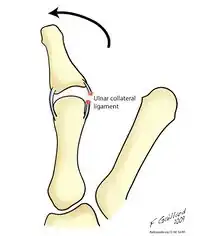

Drawing of the injury

Symptoms include instability of the MCP joint of the thumb, accompanied by pain and weakness of the pinch grasp. The severity of the symptoms is related to the extent of the initial tear of the UCL (in the case of skier's thumb), or how long the injury has been allowed to progress (in the case of gamekeeper's thumb).